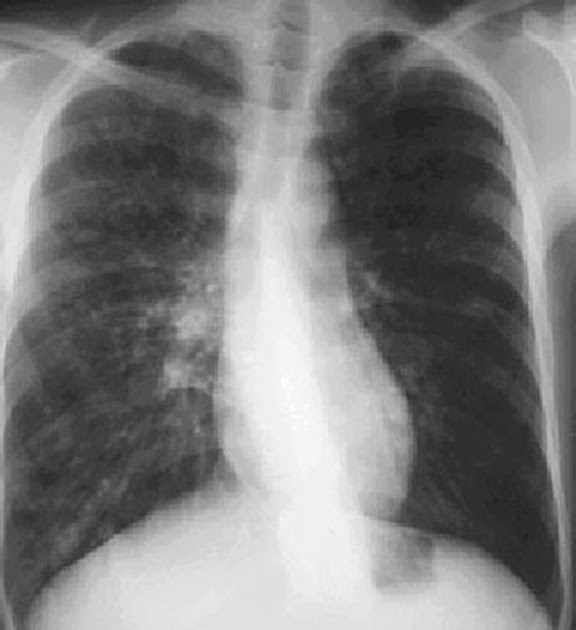

Chest Xray Film of a Patient with Bronchiectasis Stock Photo Image of

Can Bronchiectasis Be Seen On Xray A provider uses a machine to take pictures of your lungs to see if your airways are damaged. Bronchiectasis is dilation and destruction of larger bronchi caused by chronic infection and inflammation. Chest ct scan if indicated (e.g., hemoptysis, or concern for pulmonary. Accessory signs on ct that are typically associated with bronchiectasis include bronchial wall thickening and a buildup of sputum within dilated airways (see fig. When asking a radiologist about the definition of bronchiectasis, the answer will. A provider uses a machine to take pictures of your lungs to see if your airways are damaged. In the large airways, sputum and debris can occlude the airway lumen and is manifest on ct imaging as mucous plugging. Bronchiectasis and small airways disease.

From radiopaedia.org